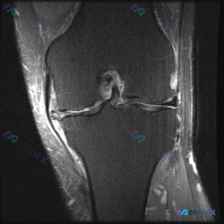

今天遇到一个挺有代表性的病例,主诉提示膝关节半月板异常,只提供了单张膝盖MRI冠状位T1加权像,整理一下分析思路跟大家分享。 一、病例核心信息 核心问题:患者主诉提示半月板异常,仅提供单一层面冠状位T1加权MRI读片 影像观察结果: 1. 骨骼:股骨远端、胫骨近端骨皮质完整连续,骨髓腔T1信号为均匀...

看到这张膝关节MRI的读片请求,目标是找半月板异常,但整理完全片发现这个病例的陷阱挺典型,分享出来给大家参考。 一、病例影像基本信息 这是一张膝关节冠状位T1加权磁共振图像,只有单一层面单序列,我们先按结构捋一遍所见: 1. 骨骼结构:股骨远端、胫骨近端骨皮质连续,没有明显骨折线;但整个骨髓腔在T1...

看到这个病例挺有代表性的:临床怀疑半月板异常,但提供的只有单张膝关节MRI冠状位T1加权序列,读片下来居然没发现明确异常,整理一下我的分析思路给大家参考。 先整理病例影像核心信息 这是膝关节MRI冠状位T1加权序列,我们先明确序列特点:T1加权主要看解剖结构,脂肪/骨髓是高/中高信号,液体、皮质骨、...